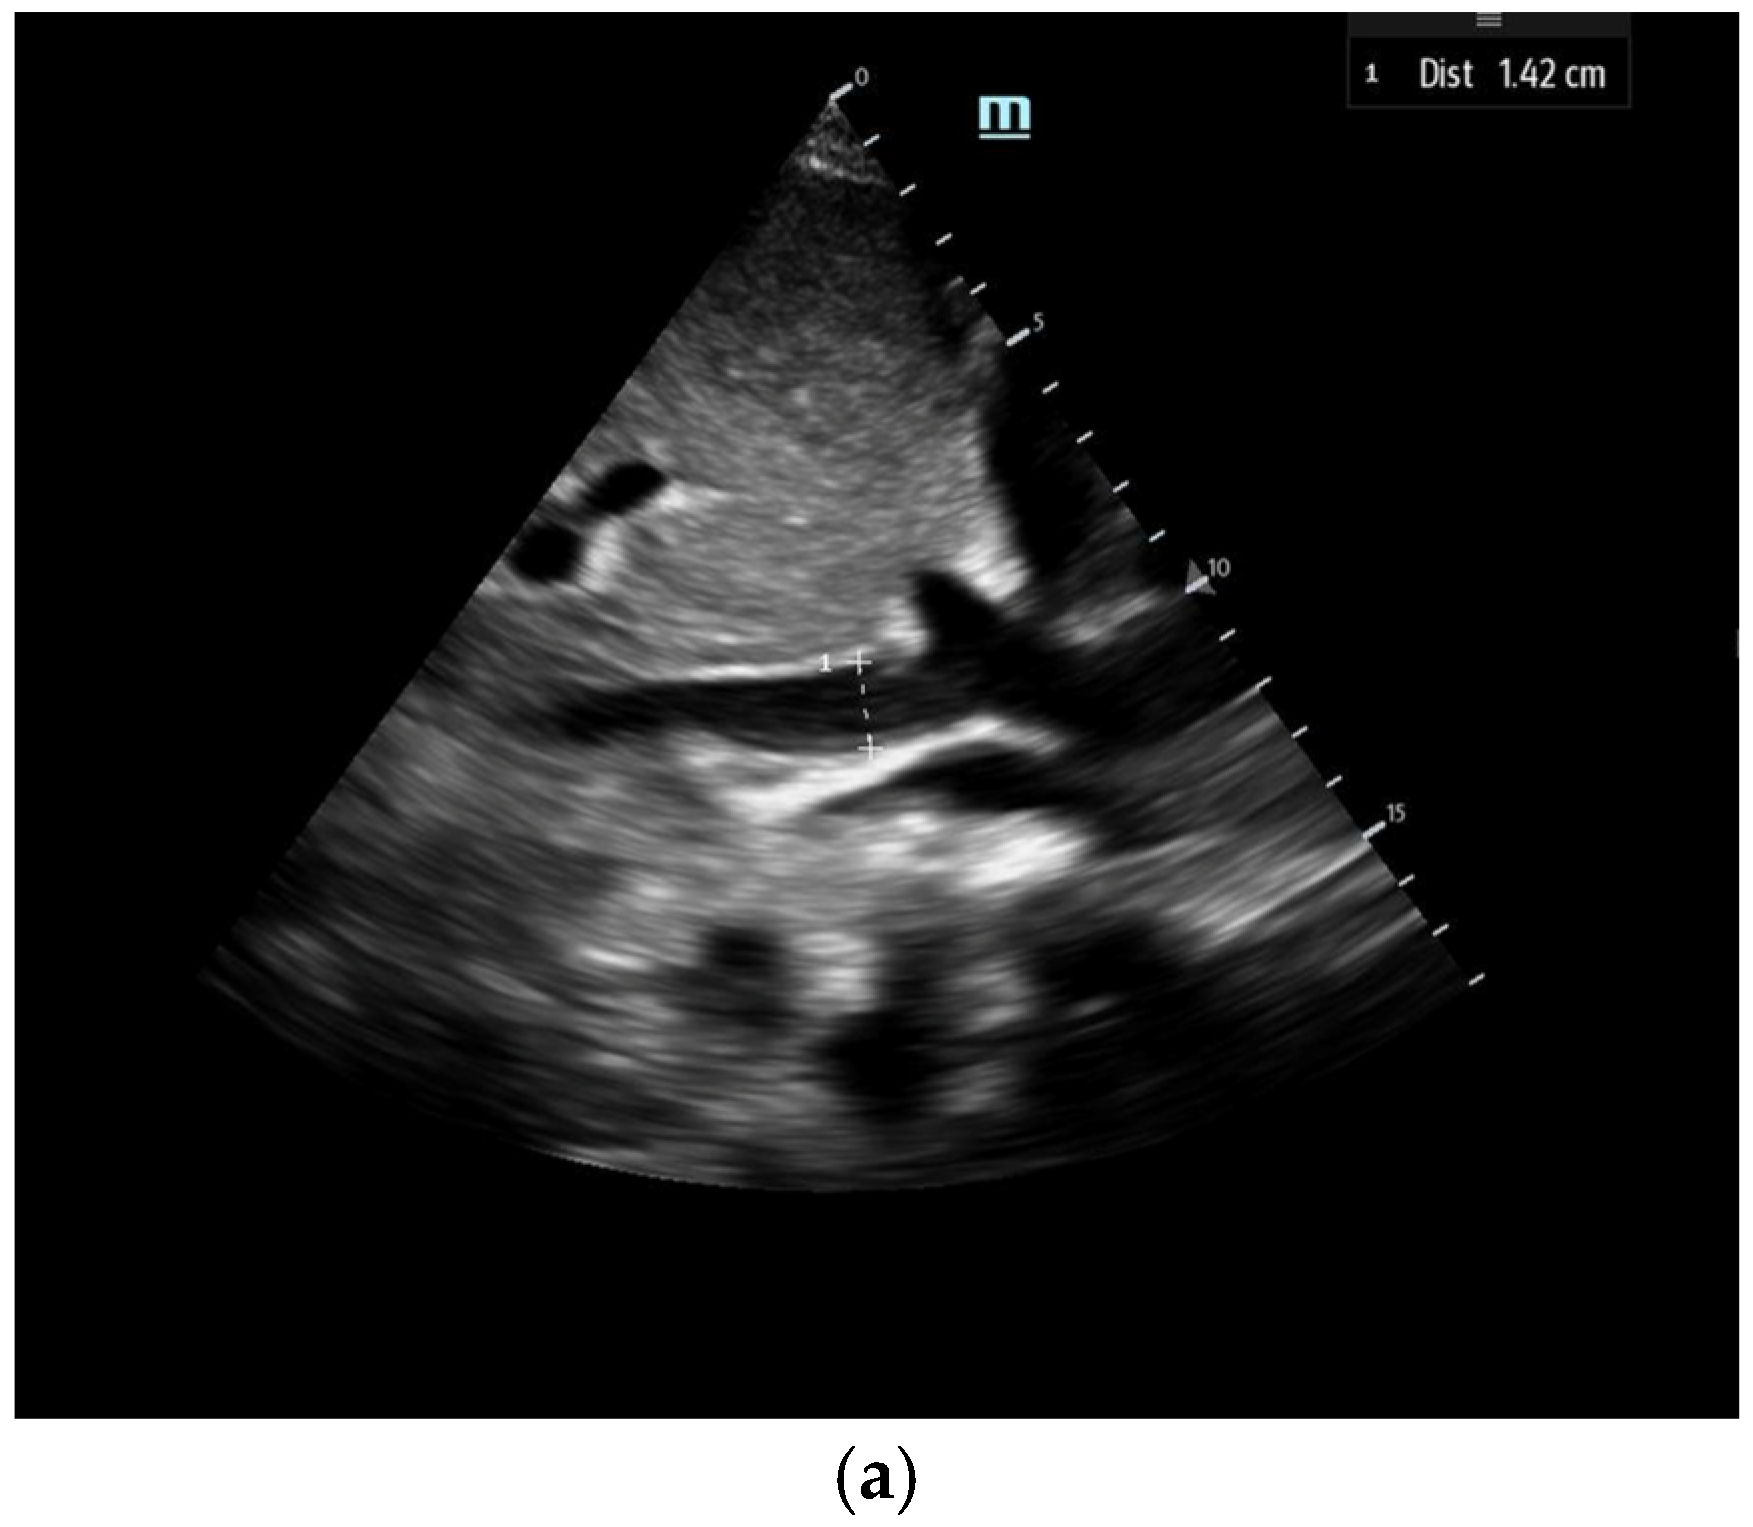

To estimate SV and CO, ultrasound requires two key measurements: the LVOT diameter and the LVOT-VTI. Cardiac output can also be indexed to body surface area to calculate the cardiac index (CI), further enhancing the hemodynamic assessment.

The LVOT diameter is measured in the PLAX view, focusing on the LVOT and aortic valve when maximally open during mid-systole (Figure 12). The measurement is taken at the base of the aortic valve, and the area is calculated using the formula:

Figure 12.

The LVOT diameter measured below the opening of the aortic valve in a zoomed-in parasternal long axis to be incorporated into the LVOT area formula.